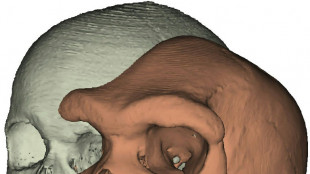

Pour comprendre l'évolution humaine, suivre la piste des sinus

Des paléoanthropologues ont réalisé la première étude d'envergure sur les sinus de la plupart des espèces humaines et grands primates, pour aider à comprendre l'évolution humaine, selon une étude parue vendredi.